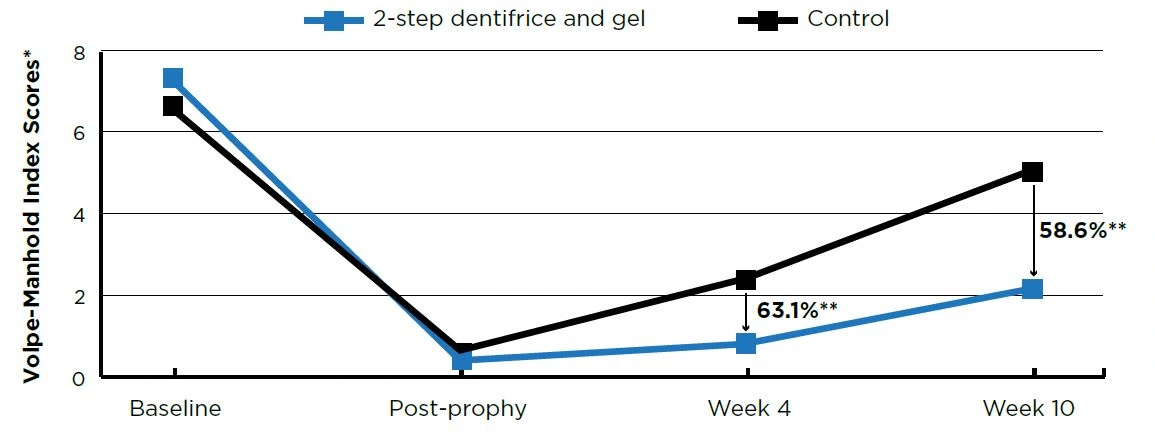

After 10 weeks of twice daily use, the 2-step dentifrice and gel system exhibited statistically lower (P<0.001) percent accumulations versus the control group in tooth stain (73.4%), plaque (30.5%), and calculus (58.6%). See Figures 1–3.

Figure 3. Calculus Scores

Figure 3. Calculus Scores

- Baseline and post-prophy scores are means; Week 4 and Week 10 scores are adjusted means. ** P<0.01

To assess the effectiveness of a daily 2-step dentifrice and gel system to prevent the formation of stain, calculus and plaque after a dental prophylaxis.

METHODS

This was a randomized, controlled, examiner-blind, 2-treatment parallel group study. Forty-eight healthy adult volunteers with evidence of plaque and either stain or calculus completed the trial.

Following a whole-mouth dental prophylaxis, subjects were randomized to one of two groups:

- Negative control - 0.76% sodium monofluorophosphate dentifrice (Colgate® Cavity Protection, Colgate-Palmolive)

- Daily 2-step dentifrice and gel system (Crest® PRO-HEALTH™ [HD]™) - Step 1, 0.454% stannous fluoride dentifrice; Step 2, 3% hydrogen peroxide whitening gel

Both groups brushed twice daily with a soft manual toothbrush (Oral-B® Indicator™, Procter & Gamble).

Stain (Lobene Index1), calculus (Volpe-Manhold Index2) and plaque (Rustogi Modification of the Navy Plaque Index3) were measured clinically prior to receiving a dental prophylaxis, immediately after a dental prophylaxis, and after 4 and 10 weeks of product use.